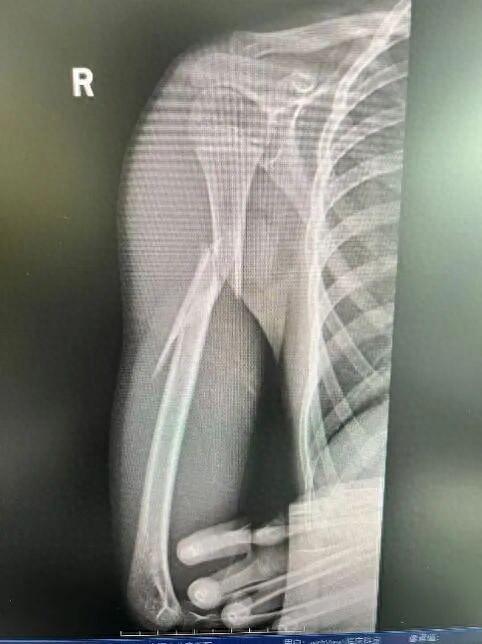

10岁男孩遭遇洗衣机“陷阱”,右臂粉碎性骨折!医生提醒

造成右肱骨干粉碎性骨折

经急诊X光检查,乐乐被确诊为“右肱骨干粉碎性骨折”。肱骨是上臂最粗壮的骨头,此类骨折通常伴随剧烈的疼痛和明显的畸形,还容易造成桡神经损伤,该神经一旦损伤,会造成永久性的功能障碍,包括无法抬手腕和翘拇指。

为最大程度减少手术创伤、避免损伤生长板、留下微小疤痕,骨科团队决定为其实施微创弹性髓内钉(TEN)固定术。与传统的大切口手术相比,这种技术仅需在骨折远端开两个微小切口,将具有良好弹性的钛合金髓内钉插入骨髓腔,像“支架”一样从内部将骨折断端对齐、固定。手术不仅时间短,而且出血少、恢复快,乐乐的手术也非常成功。术后第二天,乐乐的疼痛就大大缓解,并在医生指导下开始进行康复锻炼。他佩戴支具后已出院回家。